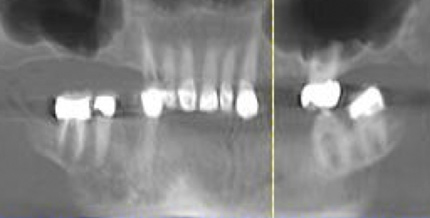

Fig 6. Panoramic radiograph of 56-year-old patient illustrating a number of dental procedures historically.

Figure 6

Interceptive implant therapy may then become a consideration earlier in life to create restorations that will not be subject to the latent effect of dental caries as aging continues. An example is shown in Figure 6 and Figure 7; the panoramic film of a 56-year-old man shows several orthognathic and extensive dental procedures historically. All full-coverage restorations had been replaced for a second time, and, again, all evidenced recurrent caries, but the existing dentition was periodontally sound and relatively esthetic.

The choice of removing a caries-challenged but restorable dentition at a younger age is ethically complex. Ultimately, the decision is the patient's alone based on informed consent of all available options. The removal of a potential lifetime of caries activity that is now more predictable than ever may be a viable option for this high-risk segment of a younger patient base.